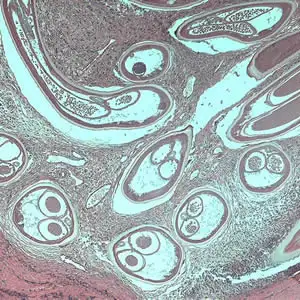

当感染性幼虫进入人体皮肤后,它们会在数月内发育成熟。雄虫相对较小,体长约2至4厘米,细如发丝;而雌虫则可达30至50厘米长,直径约0.3至0.4毫米,是名副其实的"巨虫"。成虫并不四处游荡,它们将自己蜷曲成团,深埋在皮下结缔组织中,形成特征性的纤维结节——医学上称为"盘尾丝虫结节"或"蟠尾蚴瘤"。

这些结节通常出现在骨性突起部位附近,如髋部、肋骨、肩胛骨和头颅。结节大小不一,从豌豆大小到高尔夫球大小不等,触感坚硬,通常无痛。一个感染者体内可能只有一两个结节,也可能多达数十个。在严重感染的病例中,结节几乎可以出现在身体的任何部位,包括头部和眼部周围。

然而,真正造成伤害的不是成虫,而是它们生产的微丝蚴。这些微小的幼虫体长仅约300微米,直径不到1微米,必须在显微镜下才能观察到。它们没有围鞘,身体纤细,尾部逐渐变尖。一旦离开母体,微丝蚴便开始在宿主的皮肤和皮下组织中四处迁移。